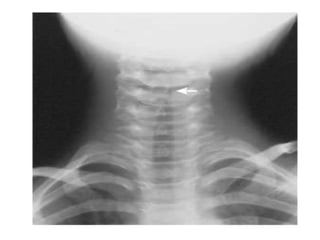

Diagnóstico:

• Es 100% clínico con exploración física

• No están recomendados estudios de

laboratorio ni radiológicos de rutina (en

dudas si)

• 16.

Diagnóstico: • Es 100%clínico con exploración física • No están recomendados estudios de laboratorio ni radiológicos de rutina (en dudas si) • El estridor no es único de LTA y refleja obstrucción en zonas superiores.